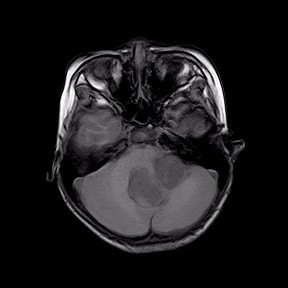

查体见四肢肌力V级,肌张力稍降低,腱反射减弱.生理反射存在,病理征未引出.闭目难立征(+),小脑共济失调征(+)。 头部MR所见:第四脑室内见一团块状稍长T1、稍长T2信号影,病灶大小约 48X33mm,病灶充满第四脑室,且向左侧桥臂侵犯,达左侧硬脑膜,病灶信号不均匀,其内可见点片状长T1、长T2囊性信号,DWI示未见明显异常受限,脑室系统明显扩张,增强扫描病灶呈轻度不均匀强化。双侧侧脑室周围白质见条状FLAIR高信号,边界不清。脑沟、脑裂变窄,中线结构居中。颅骨未见明确骨质破坏。左侧上颌窦、筛窦粘膜增厚。矢状位示垂体形态、信号未见明显异常。